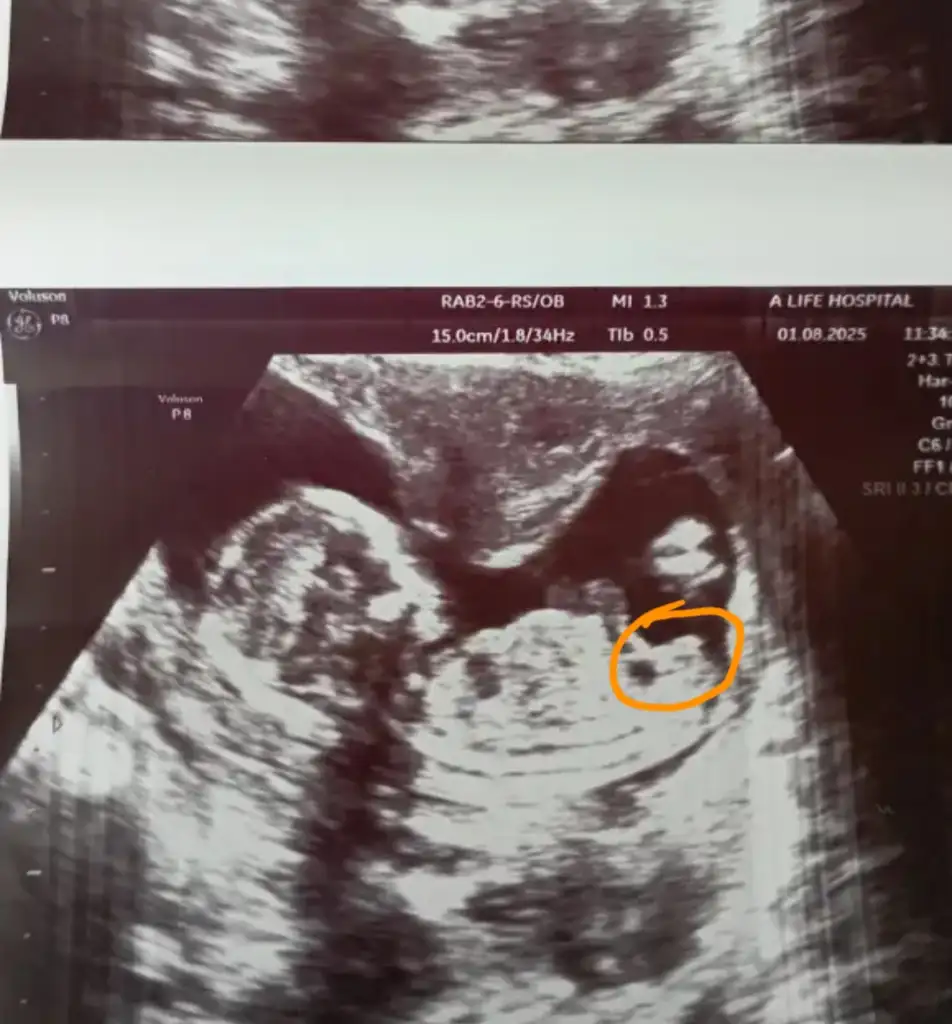

O pipi olmuyor bacak arasi değil ki o pipi olsa doktor bak bu pipi derdi herhalde açı olarak bacak arasını net görmemiz lazm bacak arasinda olmalı pipiKiz illa isaretletcen ha

Tamam ceylin daha birsey sorma banaO pipi olmuyor bacak arasi değil ki o pipi olsa doktor bak bu pipi derdi herhalde açı olarak bacak arasını net görmemiz lazm bacak arasinda olmalı pipi

Ya olabilir tabi ama ben gordugumu yorumluyorum bacak arasi fotosu yok sonucta yatay cekmis doktor benim oglumun usgsi de boyleydi pipi o sekilde gozukuyor ama kim neye inanmak istiyorsa tabiAhaha Ceylin kız istiyor heraldee

Evet o kızdada erkektede olan bisey işaretlediginin açısi önemliymişYa olabilir tabi ama ben gordugumu yorumluyorum bacak arasi fotosu yok sonucta yatay cekmis doktor benim oglumun usgsi de boyleydi pipi o sekilde gozukuyor ama kim neye inanmak istiyorsa tabi

Kiz da o sekilde bi kabariklik olmuyorEvet o kızdada erkektede olan bisey işaretlediginin açısi önemliymişoğlunun goruntu nerede at bı bakalm

Olablr blmiyorum ama bacak arasi neden hala boş pipi gözükmüyor Tamam eve nezaman gidersinkiKiz da o sekilde bi kabariklik olmuyor

Erkek demedi ya geçen hafta kız dedi bacak arasında çizgileri gösterdi kız olacak dedi ben olsam kız beklerdim dedi haftaya tekrar gel dedi bu haftada bacak arası boş gene dedi ama 17haftada tekrar gel diyor cıkınti yeni gelisiyor olablr diyor , bn diğer oglumda 15.haftada net bacak arasında pipi görmüştüm bu haftadan sonra yeni olustuguna hiç şahit olmadım net belli olsa tamamda smdi belirsizlik varCanım ne kadar uğraşırsan uğraş erkekse dönmüyorben Fetal de çıkmasına rağmen hala her gidişte doktora bakın belki değişmiştir diyorum umut fakirin ekmeği

üff sacmalamasin ya 17.haftada ne gelisecek o zamana kadar belli oluyor herseyErkek demedi ya geçen hafta kız dedi bacak arasında çizgileri gösterdi kız olacak dedi ben olsam kız beklerdim dedi haftaya tekrar gel dedi bu haftada bacak arası boş gene dedi ama 17haftada tekrar gel diyor cıkınti yeni gelisiyor olablr diyor , bn diğer oglumda 15.haftada net bacak arasında pipi görmüştüm bu haftadan sonra yeni olustuguna hiç şahit olmadım net belli olsa tamamda smdi belirsizlik var

Baya erken zamanda kız demişya banada 14.haftada söyledi kız diye çizgileri gösterdi kız genital bolgesi diye smdi iki çizgi arasından pipi çıkmasını bekliyoruz böyle bişey mumkunmuDoktor 11 haftada yuzde70 kiz demisti 12de erkek bu dedi